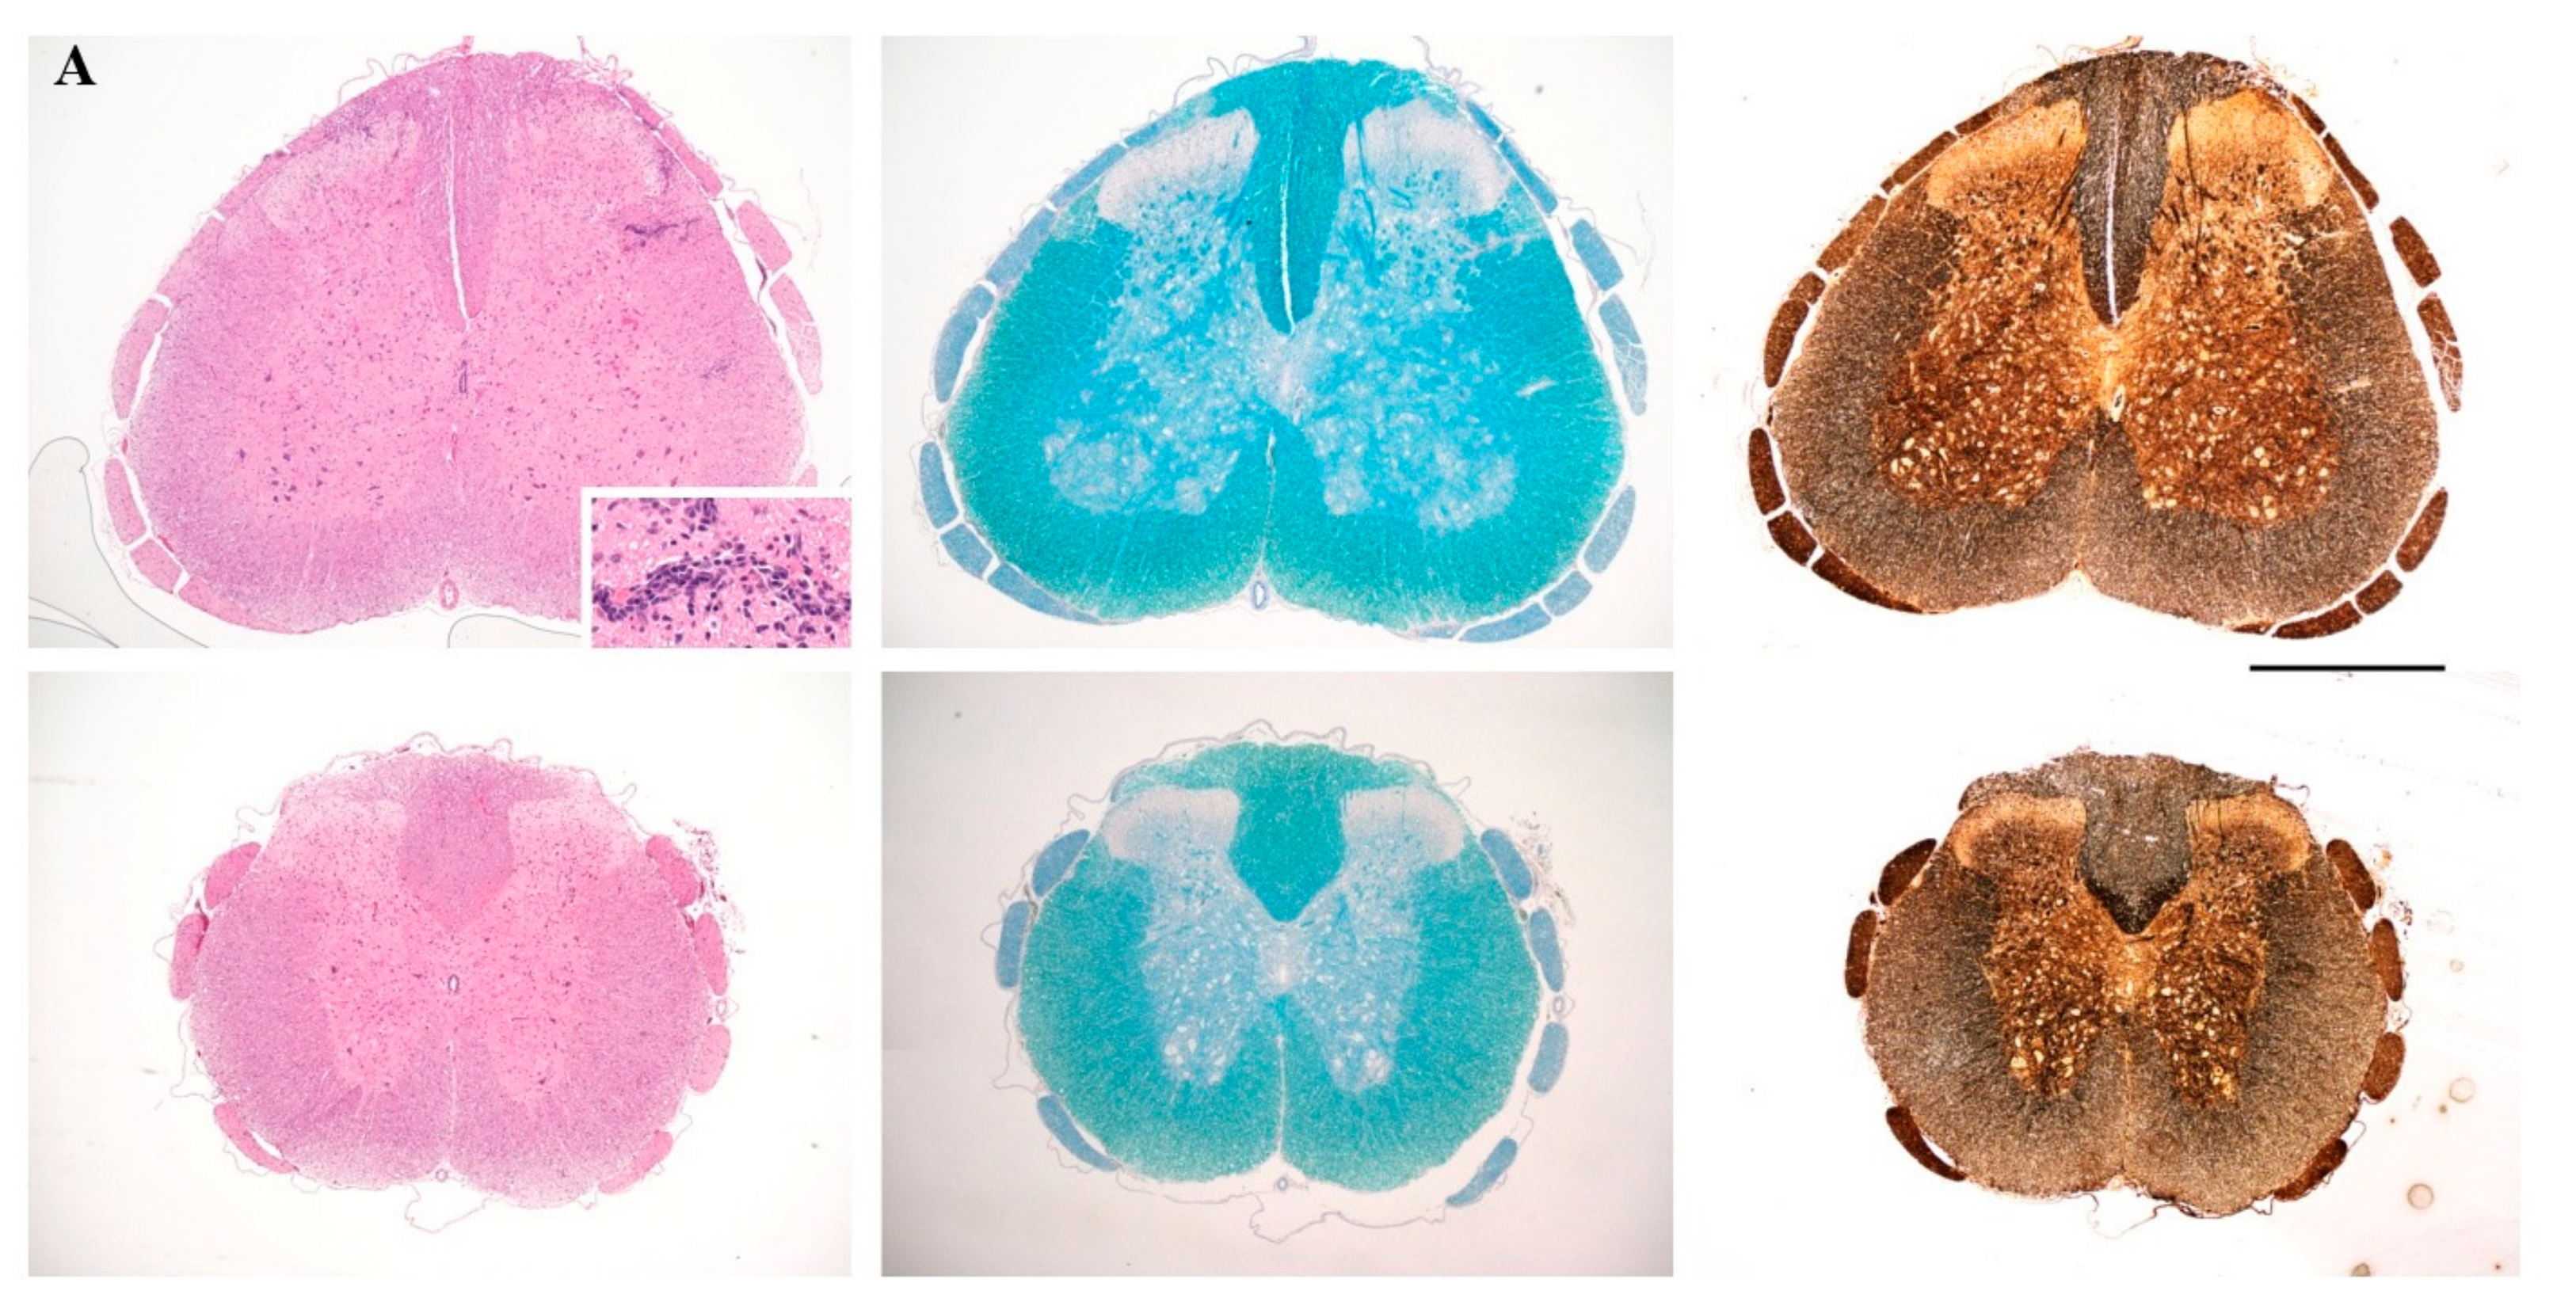

2.1. Solid-Phase Peptide Synthesis and Cyclization of the Mutated Peptide Analogues

2.4. Prophylactic Treatment with cyclo(87–99)[Arg91, Ala96]MBP87–99 Provides Lasting Protection Against MBP72–85-Induced EAE

4.5. Histopathology